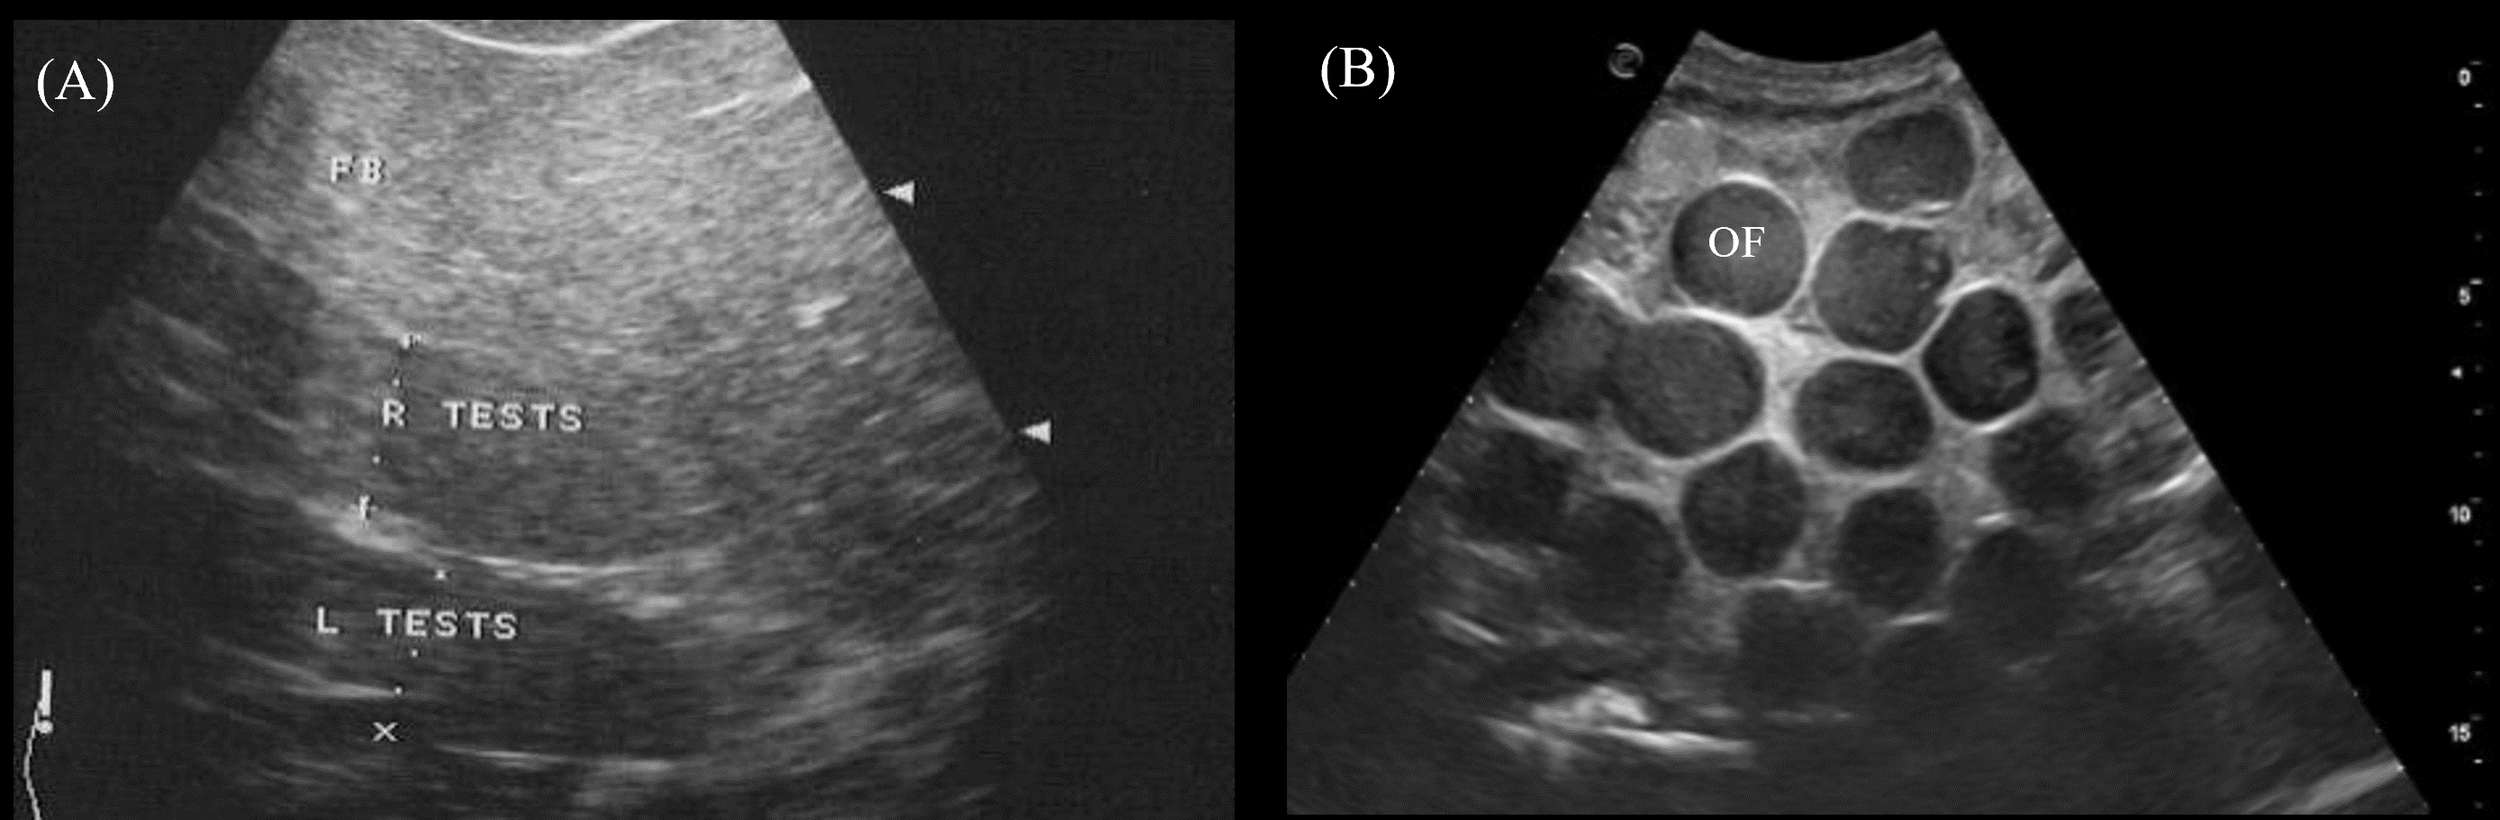

3.3.9 Gonads

The paired testes were visualized in 2/2 male crocodilians as elongated cylinders with rounded extremities cranioventral to the kidneys (Figure 3, transducer positions 4 and 8). They were homogenous and more hypoechoic than the fat body with poorly defined hyperechoic margins (Figure 14A).

Figure 14

Ultrasonographic appearance of the (A) left and right testes in sagittal view in Alligator sinensis and (B) multiple ovarian follicles with concentric anechoic centers and hyperechoic outer rims in the coelomic cavity in Caiman crocodilus. [L TEST, left testis; R TEST, right testis; OF, ovarian follicles].

In 5/5 reproductively active females, ovarian follicles were visualized in the coelomic cavity amongst the coelomic organs. The best acoustic window was via the lateral flanks just cranial to the hindlimbs and ventral to the kidneys (Figure 3, transducer position 3). The echogenicity and size of the follicles varied between and within animals depending on the stage of vitellogenesis. Most commonly seen were spherical ovarian follicles with a concentric anechoic center and hyperechoic outer rim (Figure 14B). Some ovarian follicles had an anechoic core and hypoechoic middle with a hyperechoic outline.